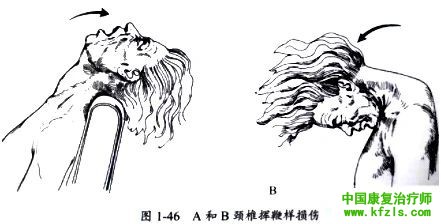

患者常由于在车祸时颈部急剧往前、后甩动(挥鞭样损伤)或者扭转而导致颈部疼痛(图1-46)。这种损伤会造成神经根牵拉并撞击至周围骨赘上, 或直接导致椎间盘突出。

有神经受累的患者主诉颈痛,范围可涉及肩胛骨内缘和不同程度的上肢放射痛,并可伴有肢体麻木及肌无力等症状。但是,需注意单纯颈部肌肉损伤也可出现相似症状。

神经损伤与软组织损伤的鉴别需要进行全面的上肢神经系统体格检查。由于可能存在迟发临床症状,因此患者每次复査时均需重复进行神经系统体格检查。